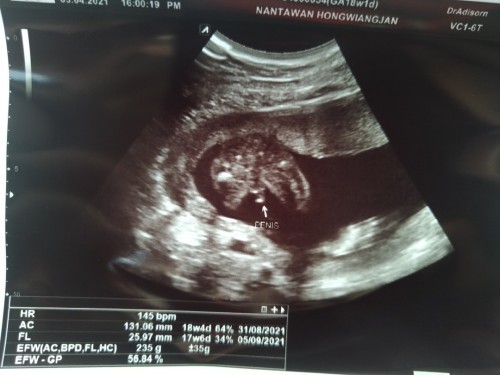

บ้านนี้ 18W3D ลุงหมอบอกได้เพศชาย

บ้านนี้ก็ผู้ชายค่ะ ชัดมาก 😂

Nantawan Hongwiangjan

17w บ้านนี้ผู้ชายจ้า